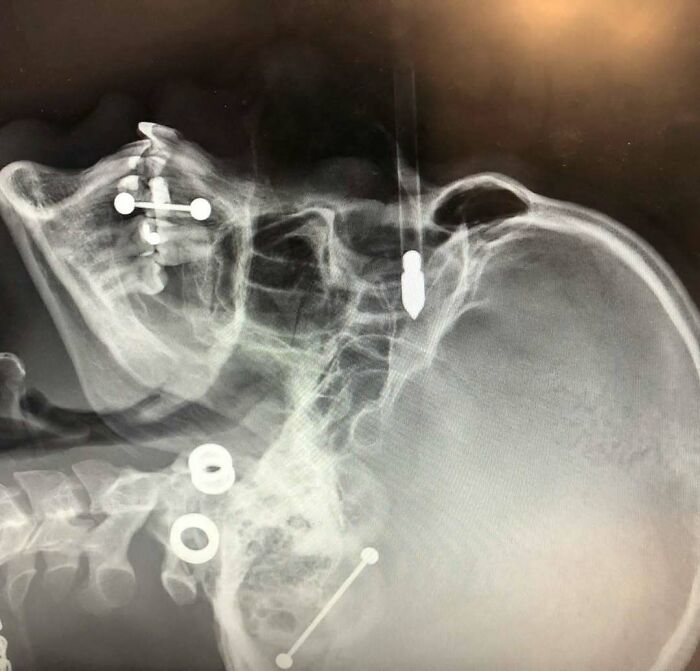

#54 A 15-Year-Old Boy Has Three Extra Vertebrae In His Neck

A Condition Known As Supernumerary Vertebra Along With Congenital Scoliosis - Causing Pain, Stress On His Nerves, And Making It Difficult For Him To Walk.